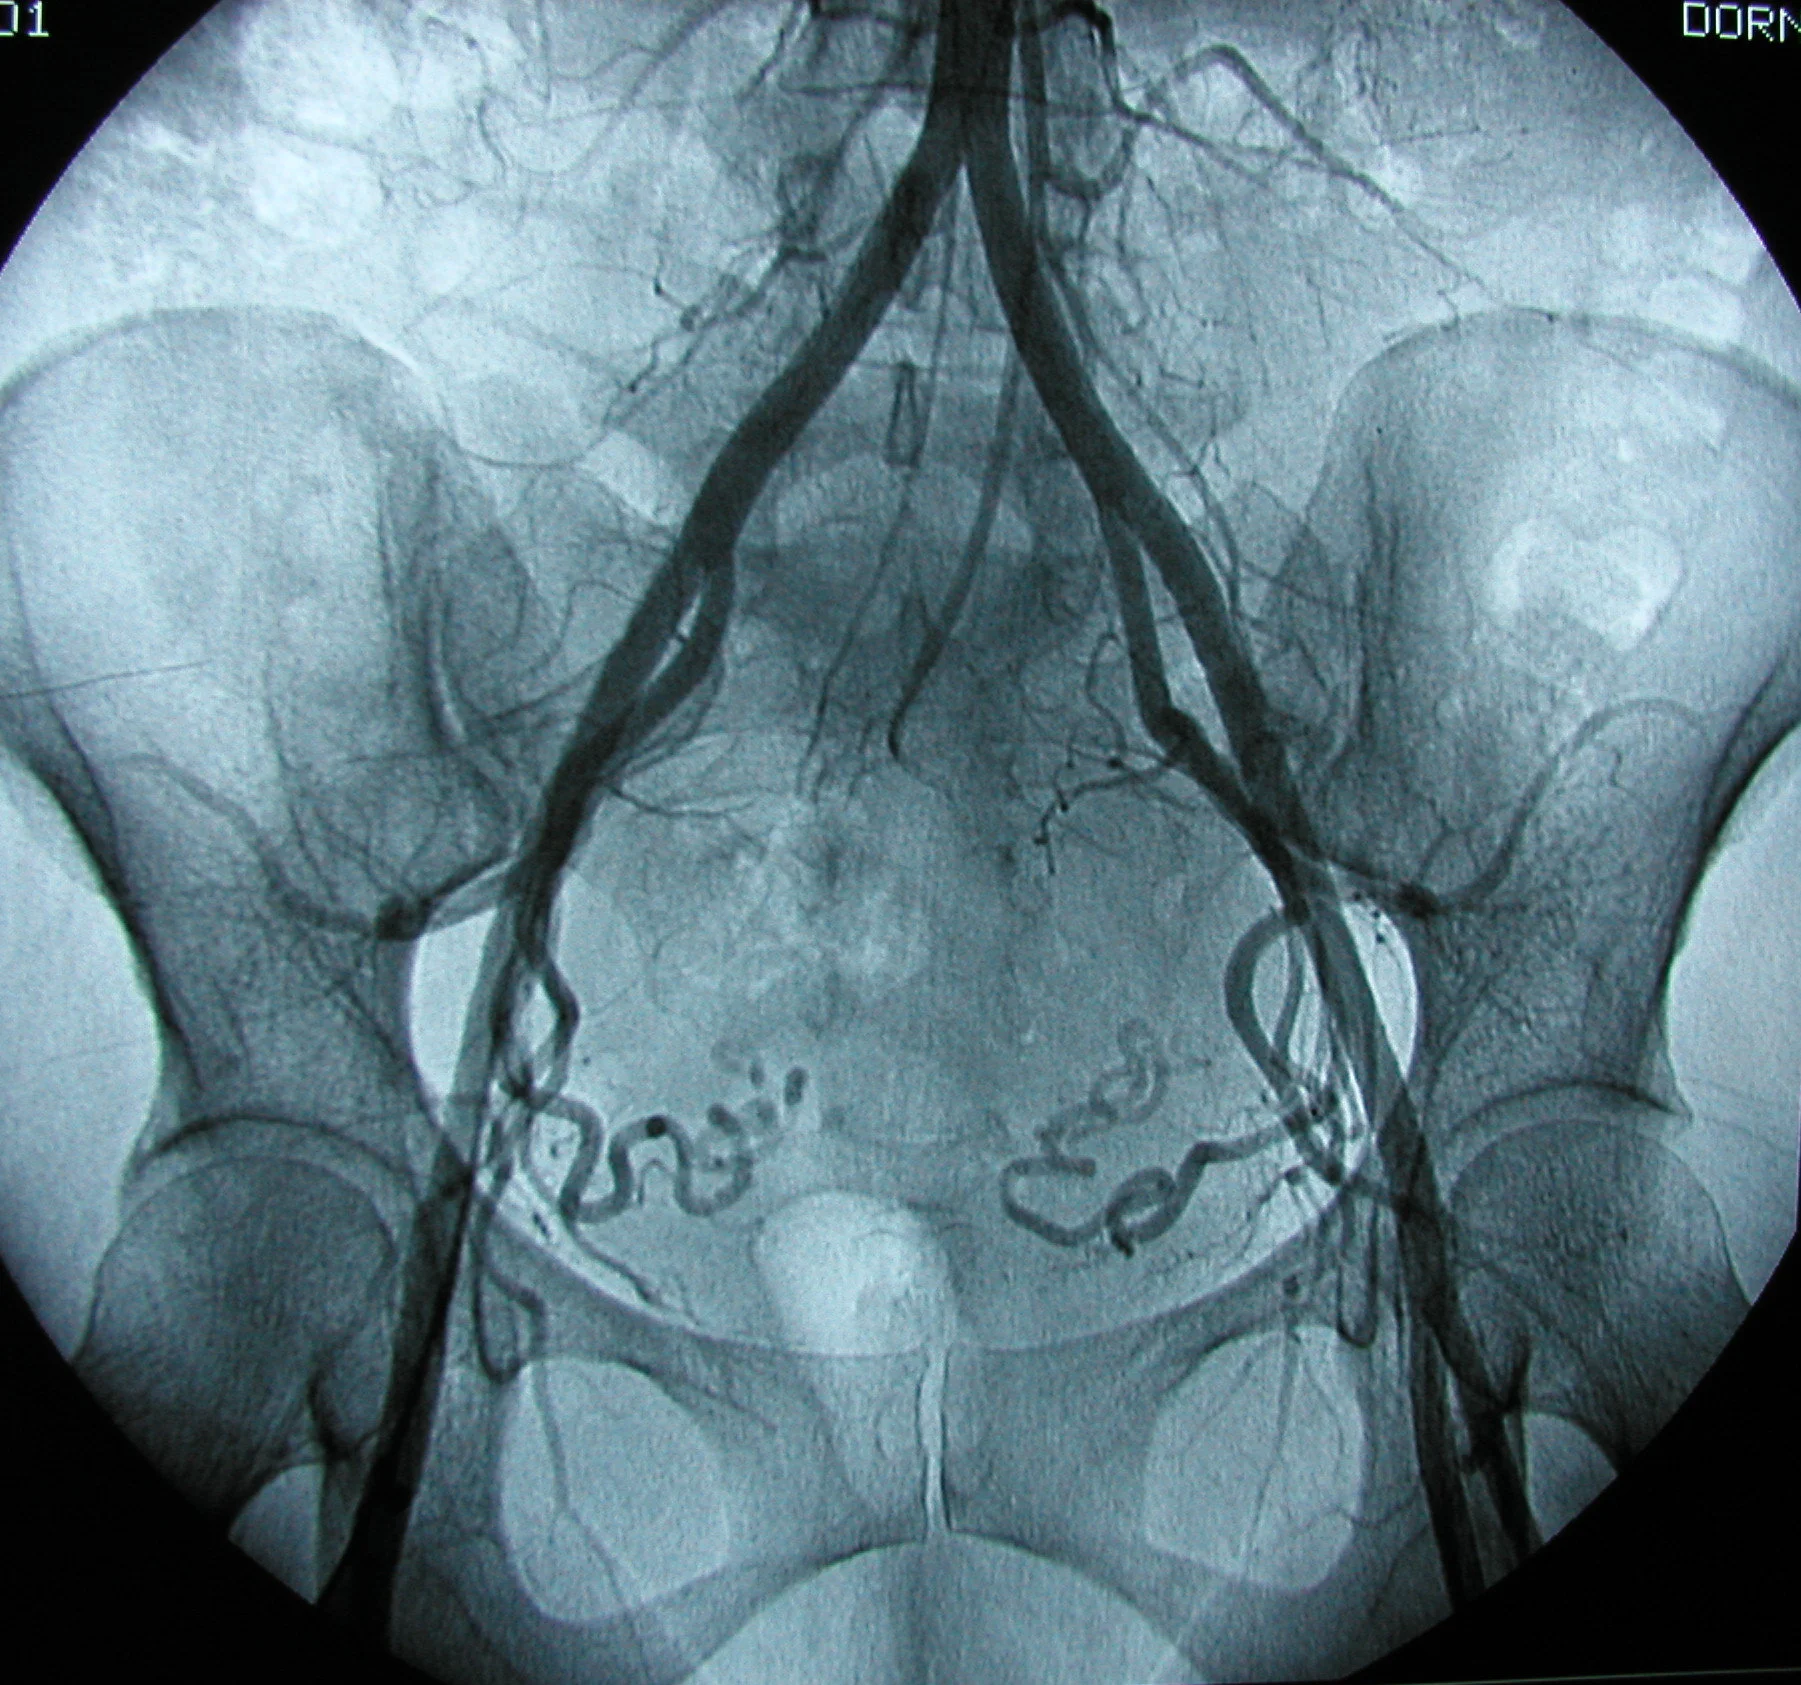

Peripheral Intervention 9.jpg